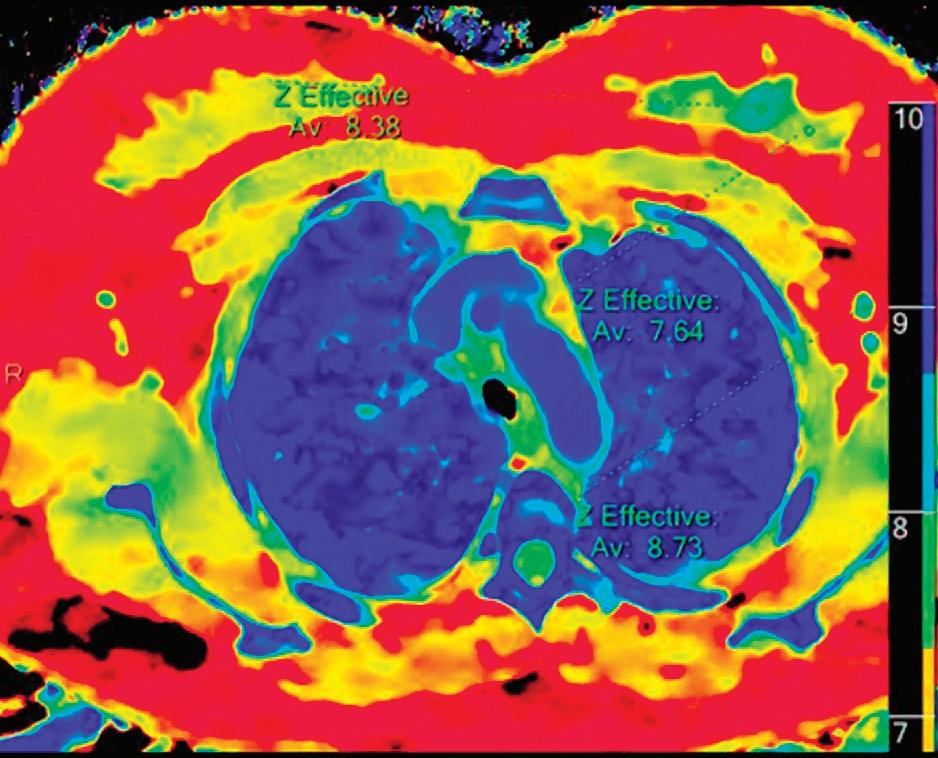

Z Effective (Zeff)

Effective atomic number. Each voxel is set to a value in the range 5 to 30 representing the effective atomic number of that voxel. Z effective of air is set to zero. For reference, Z effective of water is 7.4, Z effective of cortical bone is 13.2, and Z effective of fat is 5.9. Z effective maps are very sensitive to materials characteristics (Figure 3) and can also be used to display perfusion maps and to identify very subtle perfusion deficits (Figure 2b). The accuracy measured on a Gammex phantom with iodine, calcium, and soft tissue inserts show that the majority of Z effective values are within 0.2 Z effective units and are consistent between 120 and 140 kVp scans.21